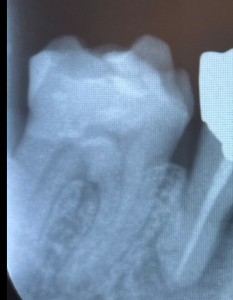

パノラマエックス線撮影と主訴である右下の口腔内エックス線撮影を行いました。

1日目 パノラマエックス線検査、虫歯の有無の確認、歯周病の検査を行いました。

パノラマエックス線検査は、エックス線の透過度の違いにより、歯や骨といった硬組織が白く映ります。エックス線の透過性から骨の形を知ることができます。